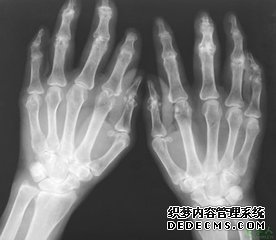

关节炎有什么症状和临床特征?在关节炎的多发部位中,膝关节是其中之一。关节炎是指由于膝关节软骨变性、射精障碍而引起的一种慢性骨关节疾患,又称为膝关节增生性关节炎、退行性关节炎及骨性关节病等。那么关节炎的症状和临床特征是什么呢,下面一起来看看阿拉尔男科医院专家的介绍。

可为单发性,或双侧性,女性偏多且往往是体重超标者。中年后的症状:当坐起立行时觉得膝部酸痛不适,走了一时症状消失,这是早期表现。

随着关节炎疾病的发展,活动并不能缓解疼痛,且上下楼梯或下蹲与座起站应都有些困难,需手在膝盖上撑助才行。多走之后膝关节有些肿,或肿得厉害,还可以抽出一些淡黄色液体。由于滑膜与关节囊有病变而增厚,活动时可有响声,如果是关节内有游离体形成,可影响关节活动,并不时有"关节绞锁"现象。到最后出现膝关节畸形,例如膝关节屈曲挛缩,O形腿或X形腿,甚至拄拐杖才能行走。